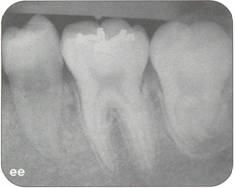

Fi 545e45f g 5-8ee Six weeks after transplantation. Fi 545e45f g 5-8ff Clinical view 6 weeks after trans plantation |

Fi 545e45f g 5-8gg Three months after transplantation. Inflammatory root resorption is ob. served on the distal aspect of the donor tooth. Root canal therapy was started immediately. Fi 545e45f g 5-8hh One month after temporary obturation with calcium hydroxide. Arrest of root resorption was confirmed and orthodontic treatment was started. |